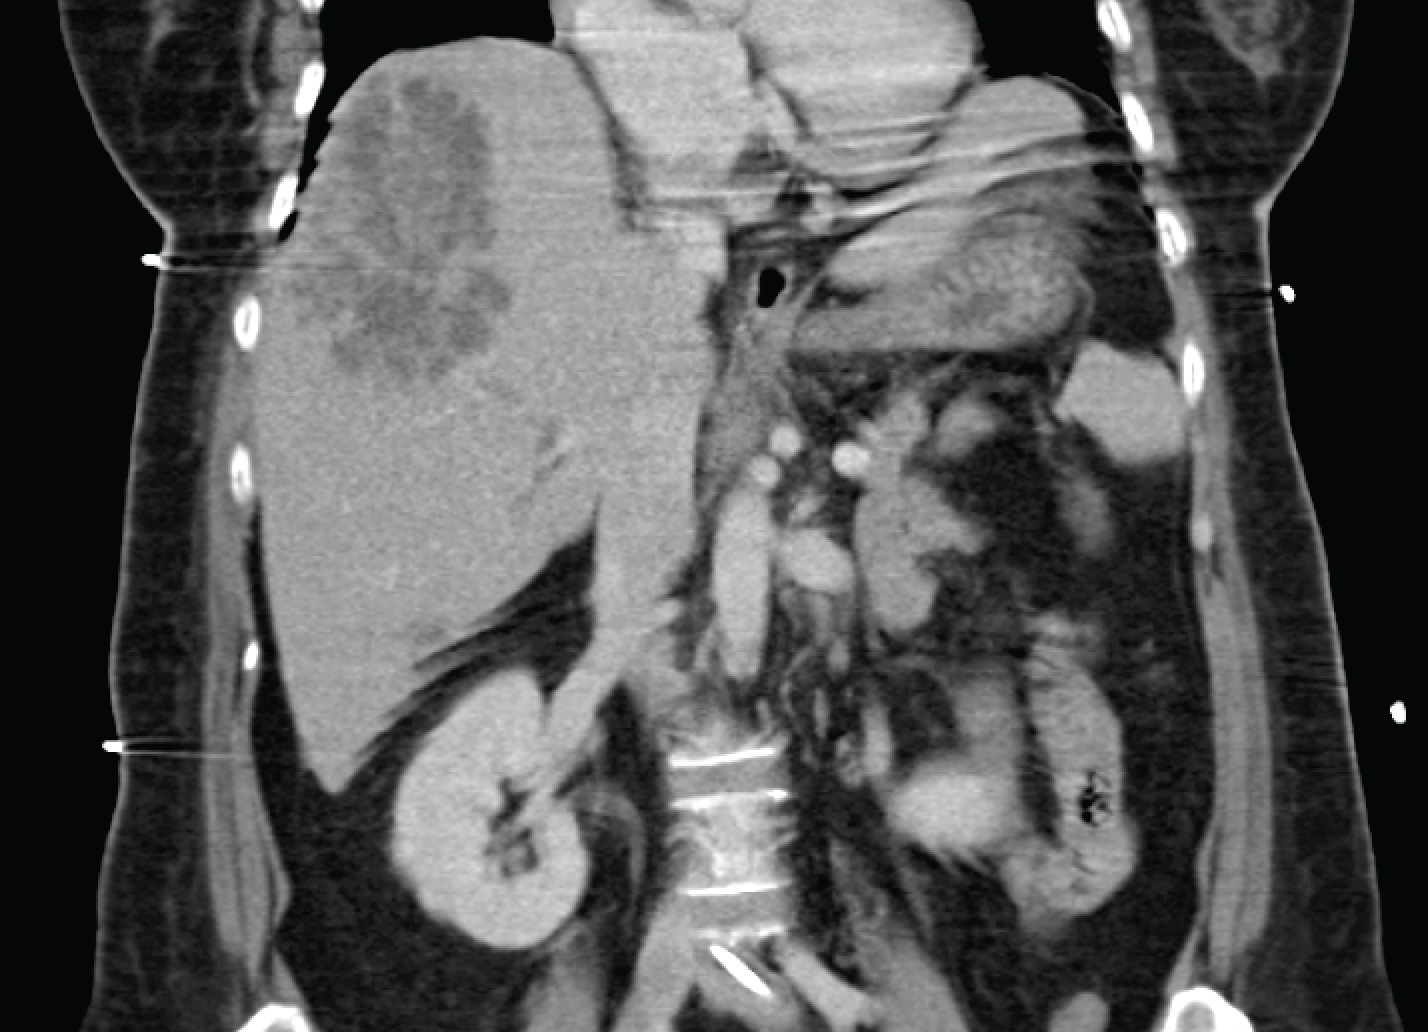

A middle-aged man in his late 50’s presented with fever for 3 days associated with poor appetite and epigastric discomfort. He had been prescribed augmentin by his general practitioner 2 days ago without relief of symptoms. His only premorbid conditions were hypertension and hyperlipidemia, and there was no travel or contact history of significance. Physical examination revealed right hypochondral tenderness, and a CT abdomen was ordered.

In a patient from the community, and in Singapore, this is almost invariably Klebsiella pneumoniae liver abscess. This is the same type of Klebsiella pneumoniae that can cause endophthalmitis as described previously (one can also find some nice pictures and a short microbiological description here).